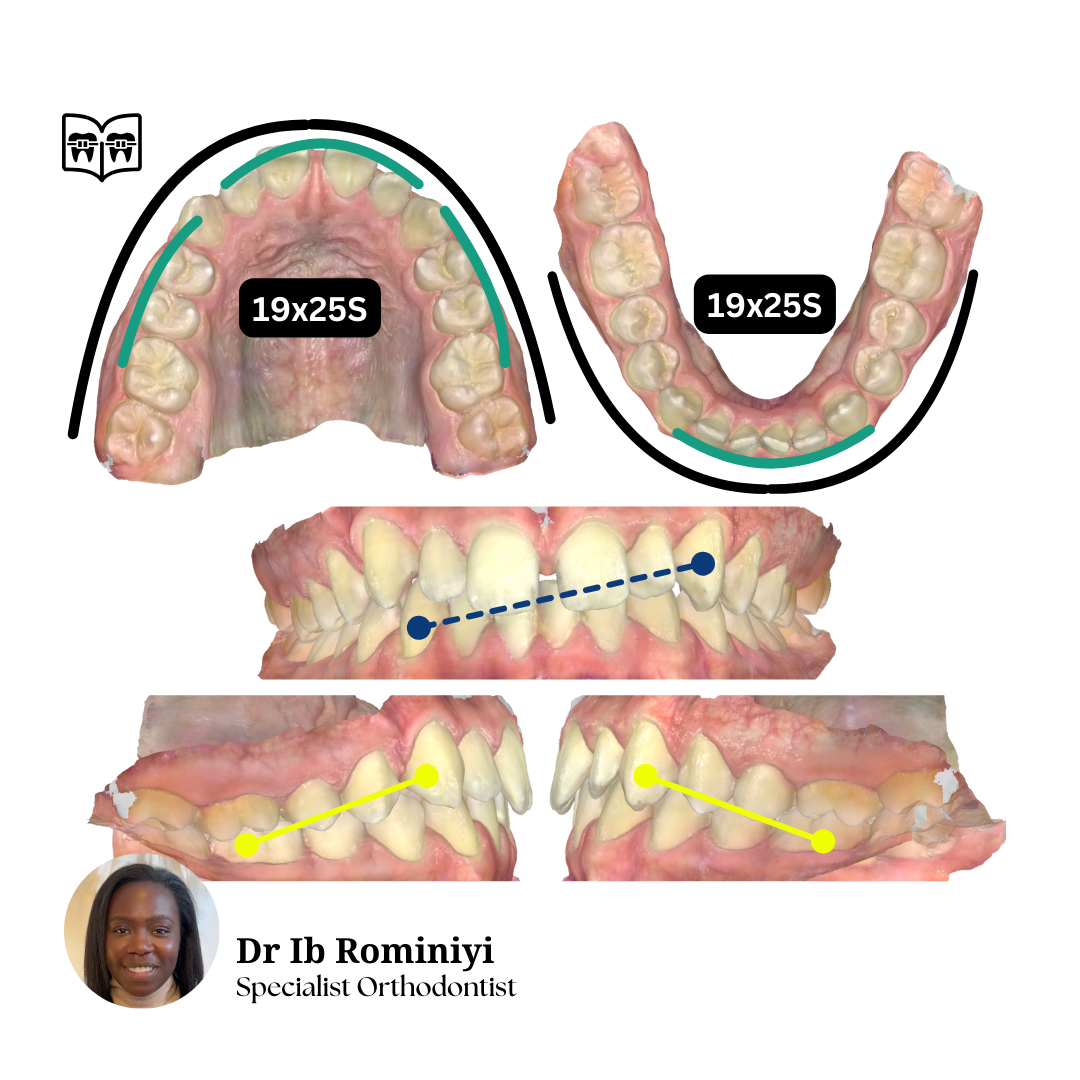

M E N T O R I N G M O M E N T

#1

Dentist's Question: I'm currently in upper 19x25N, lower 18x25S and the lateral open bites and centrelines are getting worse.

How would you improve the bite?

What mechanics & archwires would you use from here?